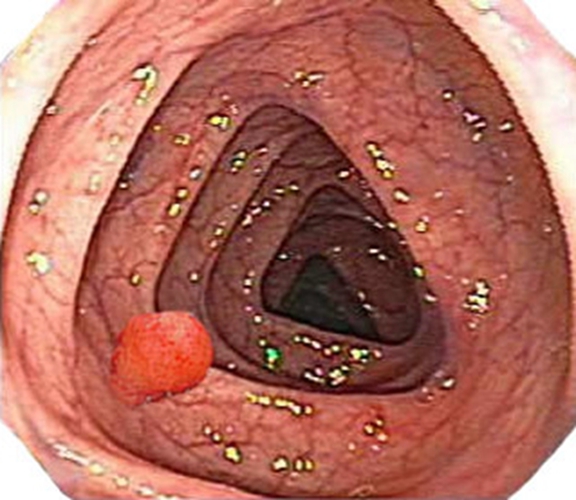

痔瘡的主要癥狀包括肛門疼痛、瘙癢、出血等,在痔瘡圖片真實(shí)癥狀圖片中,我們可以看到痔瘡的具體表現(xiàn),如肛門周圍的腫塊、出血點(diǎn)等,以下是痔瘡常見(jiàn)的一些癥狀:

1、內(nèi)痔:內(nèi)痔主要位于肛門內(nèi)部,早期可能無(wú)明顯癥狀,隨著病情發(fā)展,可能出現(xiàn)出血、痔核脫出等癥狀。